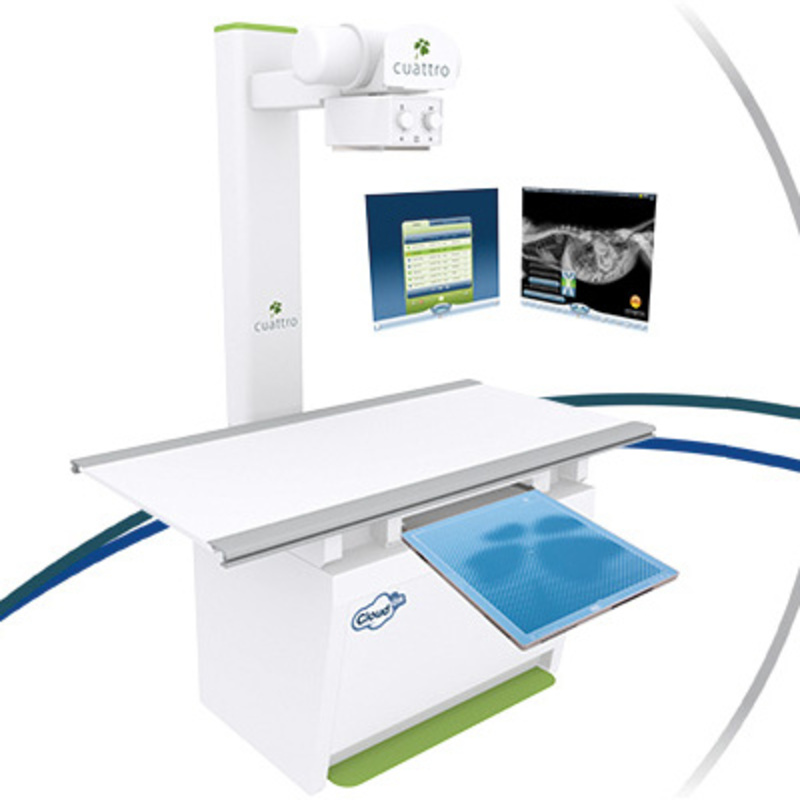

Générateur cuattro DR uno CA

Au delà de l'excellence vétérinaire !

Description du produit

Générateur SEDECAL cuattro

- Générateur haute fréquence 32 kW

- Anode tournante, double foyer 1 et 2 mm

- 40 à 125 kV (85 paliers)

- 10 à 400 mA

- Plateau 4 voies

- Collimateur 43x43 cm

- Pilotage des constantes par station cuattro

Capteur plan haute définition 100 µm

- Grande surface active 43x43 cm

- Scintillateurs Csl (Tl)

- AED (Auto Exposure Detection)

- 16 bit

- Résolution : 100 µm

- Traitement : 2 à 4 sec

Station d'acquisition cuattro

- PC "tout en un" de 24 pouces tactiles

- Logiciel uno small animals

- Zoom, ROI, mesures, luminosité/contraste

- Mode comparaison études ou séries

- Affichage des constantes de tir

- Examens anatomiques préréglés

- Enregistrement des tirs pour PCR sous Excel

- Standard Dicom 3.0, 10 et Worklist

- Exportation des clichés en DICOM, JPEG par USB, HDD, CD, PACS

- Programmes : anatomique, KV/mAs, KV/mA/s

Archivage

- HeskaView+

- PACS sur le CLOUD : éditez, partagez et archivez en toute sécurité vos données. (Compatible Android et Apple)